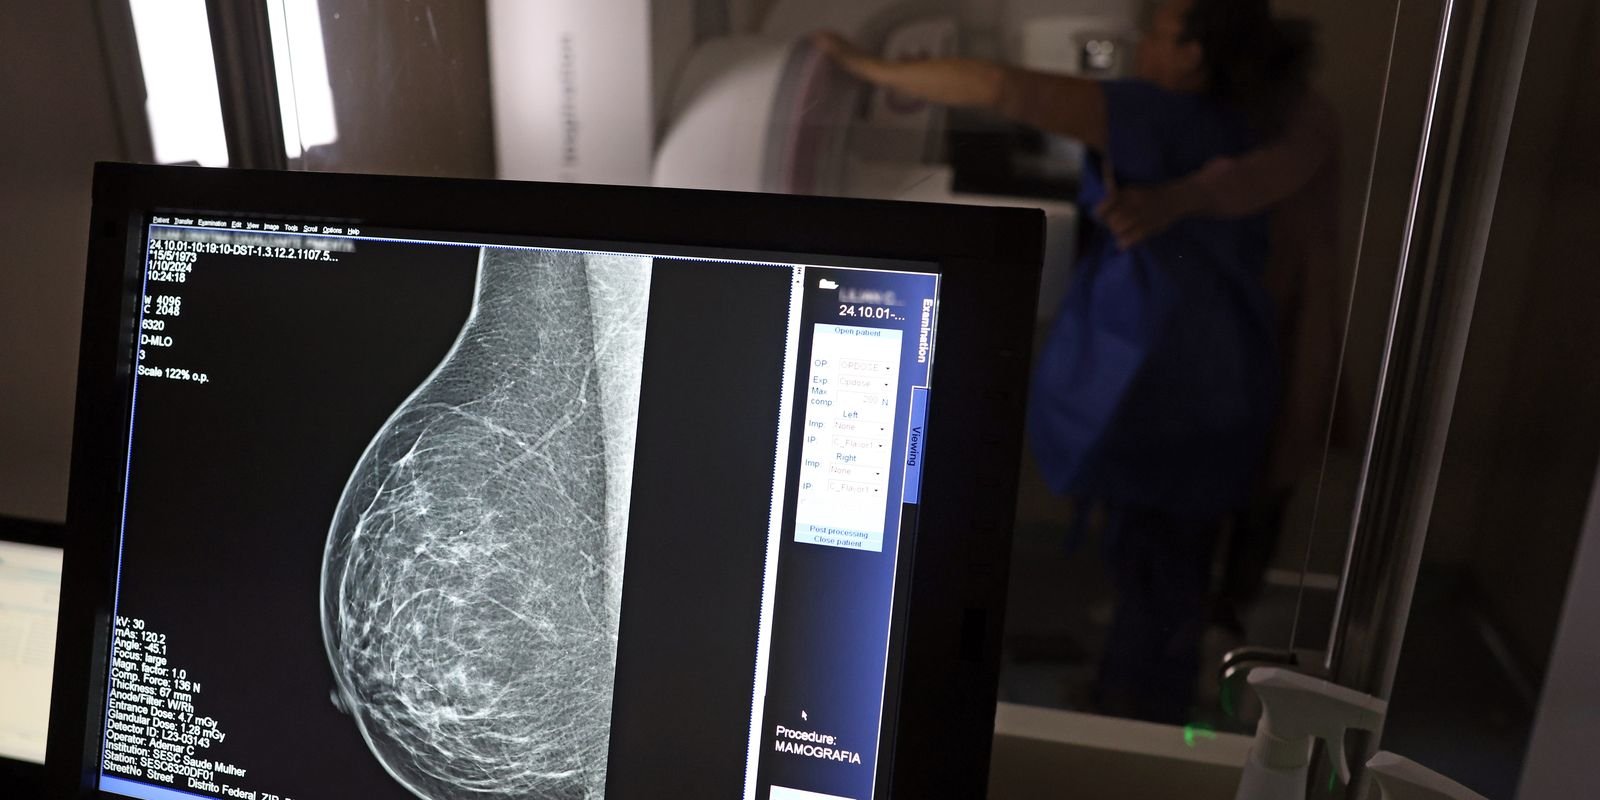

Falta de acesso a mamógrafos limita prevenção do câncer de mama

No mês de conscientização sobre o câncer de mama, um relatório destaca a importância de acesso igualitário ao rastreamento e tratamento da doença. Segundo o Atlas da Radiologia no Brasil, do Colégio Brasileiro de Radiologia e Diagnóstico por Imagem (CBR), o acesso aos mamógrafos ainda é um desafio.

“O que é efetivo na redução da mortalidade é você descobrir o tumor antes de ter sintoma clínico. Quanto menor o tumor, melhor para a gente descobrir o tratamento e maior a chance de cura. E a gente só consegue fazer isso com exames de imagem”, diz Ivie.

Ela explica que no caso de diagnóstico de um câncer de mama com menos de 1 cm, a chance de cura é de 95% em cinco anos, independentemente se ele é do tipo mais agressivo. “E esses tumores só vão ser detectados na mamografia. Essas pessoas que têm que ir fazer mamografia são mulheres saudáveis. Não são mulheres doentes”, acrescenta.